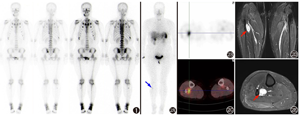

患者女,37岁,1年前无明显诱因出现腰背部及右下肢疼痛,影响行走。就诊于本院骨科门诊,门诊体格检查见患者步态不稳,拖腿行走,下蹲后可站立,腰椎活动受限。为明确腰腿痛原因,患者行腰椎MRI、骶髂关节X线摄影和全身骨显像。腰椎MRI提示多发椎体终板炎,L3~L5椎间盘膨出,L3~L5棘间韧带变性。骶髂关节X线摄影提示右侧骶髂关节间隙变窄。99Tcm-亚甲基二膦酸盐(methylene diphosphonate, MDP)全身骨显像(图1)示中下段胸椎及腰椎上终板显像剂摄取增高,双侧胸锁关节、双侧多根肋骨与肋软骨交界区摄取增高,双侧骶髂关节及耻骨联合摄取增高,另在右侧第10后肋、左侧第10肋椎关节区、右侧腓骨上段、右侧下颌骨等见多处摄取增高灶。

那么,本例患者是否为TIO?如果考虑TIO,如何确定致病灶?仔细回顾患者全身骨显像的图像,可发现"右侧腓骨上段"的摄取增高灶,并非位于骨骼本身,而是定位在胫骨与腓骨之间,为1处骨外摄取灶。TIO的责任病灶一般为磷酸盐尿性间叶组织肿瘤(phosphaturic mesenchymal tumor, PMT),可发生在全身骨骼及软组织,软组织肿瘤多见于大腿,其次为足;骨肿瘤多见于四肢骨,其次为躯干骨,而颅面骨少见[4,5,6]。PMT与TIO的发生有很强的关联性,原因为PMT异位表达并分泌成纤维细胞生长因子23(fibroblast growth factor 23, FGF23)及其他促进尿磷排泄的蛋白质,多数患者循环血中FGF23的水平增高,可降低肾脏近曲小管对磷酸盐的重吸收及1,25-(OH)2维生素D的生成,导致低血磷性骨软化症[7,8]。基于右小腿病灶的发现及以上分析,考虑患者很可能是肿瘤导致的低磷骨软化症,责任病灶可能为右侧胫腓骨间的骨外摄取灶。

由于绝大多数PMT有高表达2型生长抑素受体(somatostatin receptor 2, SSTR2)的分子特征,因此SSTR显像是诊断TIO的重要影像学检查方法[9]。患者行99Tcm-联肼尼克酰胺(hydrazinonicotinamide, HYNIC)-酪氨酸3-奥曲肽(Tyr3-octreotide, TOC) SPECT/CT显像(图2A,图2B,图2C)见右侧腓骨上段旁肌肉间隙内SSTR高表达灶,与全身骨显像所见病灶部位一致,支持为TIO。小腿MRI(图2D,图2E)见右侧腓骨上段旁软组织内椭圆形等T1稍长T2信号,大小约3.7 cm×1.9 cm×1.5 cm,超声亦提示右侧腓骨旁肌层内低回声病灶,大小3.3 cm×2.4 cm×1.7 cm。患者随后行手术切除该病灶,病理证实为PMT,术后2周复查血磷恢复正常(1.37 mmol/L)。